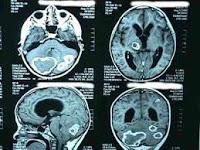

Un ensayo de fase II

presentado en la reunión anual de la Sociedad de Cuidados Neurocríticos en Scottsdale, Arizona, Revista Salud y Bienestar